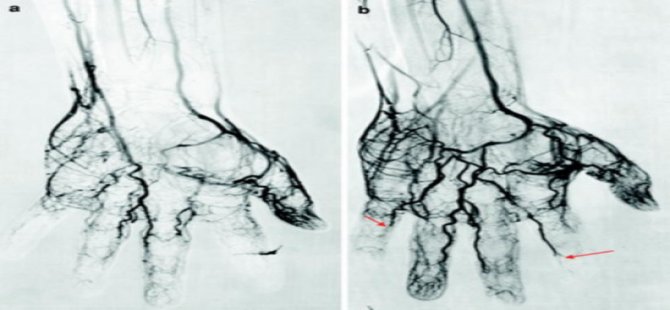

Buerger hastalığı sebebiyle damarlarda tıkanmalar yaşanır. Bu durum parmaklara giden kan akışını azaltır, zamanla parmakları, elleri ve ayakları etkisine alan hastalık, uzuv kaybına kadar götürebilir. Hastalığın etkisiyle iyileşmeyen yaralar kangren ile sonuçlanabilir. Dolayısıyla kangrenli uzuvlar kesilerek çevre dokuların korunması amaçlanır. Bu sağlık problemine halk arasında budama hastalığı denmesinin sebebi de tam olarak budur.

Tedavi için kan akışını arttırmaya yönelik işlemler yapılabilir. Kılcal damarını genişleten ve pıhtıların erimesini sağlayıp kanı akışkan hale getiren bazı ilaçlar ilk aşamada etkili bir başlangıçtır. Bunun yanı sıra bypass cerrahisi de uygulanabilir.